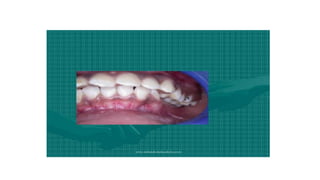

Types of Malocclusions •Overcrowding.Overcrowding is a common condition typically caused due to lack of space resulting from overlapping or crooked teeth. •Spacing. ... •Openbite. ... •Overjet. ... •Overbite. ... •Underbite. ... •Crossbite. ... •Diastema.